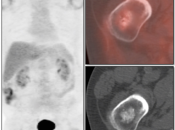

Recurrence & Restaging:

- PET/CT is utilized for patients with known or suspected recurrent disease (or at high risk for recurrence).

- Distinguishing recurrence from post-therapeutic inflammation/scarring at operative site.